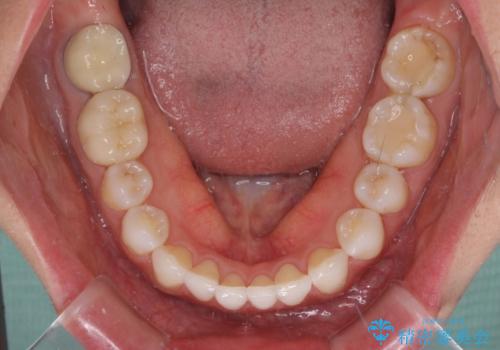

- 前歯が気になるとのことで来院された患者様です。

歯列不正は軽微であったため、インビザライン・ライトにより、費用を抑えて矯正治療を行うこととしました。

短期間で気になる前歯の歯列を改善することができました。